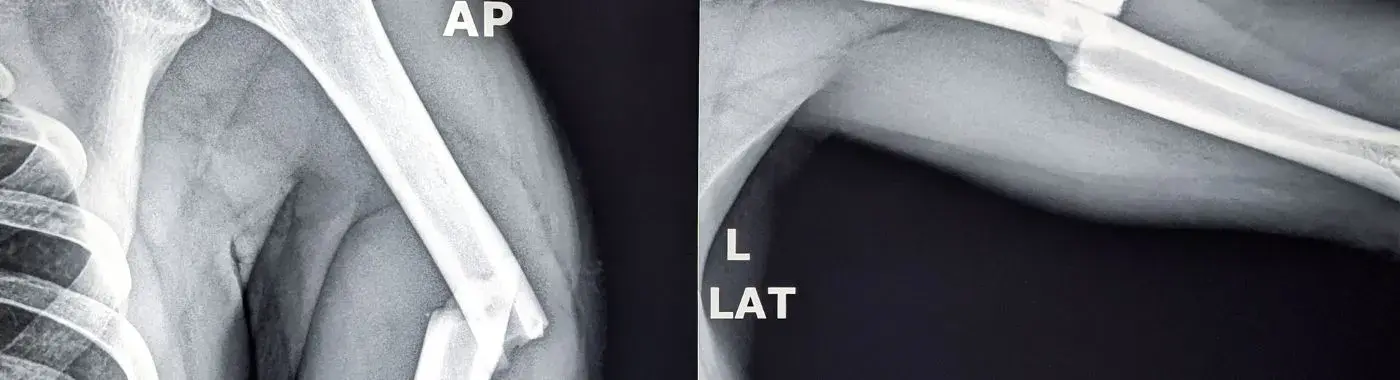

• Imaging Studies: X-rays are the primary imaging tool used to confirm the presence of a fracture. In some cases, CT scans or MRIs may be necessary for a more detailed view.

It is essential to differentiate compound fractures from other types of injuries, such as sprains, strains, or simple fractures. A healthcare provider will consider the patient's symptoms, history, and imaging results to make an accurate diagnosis.